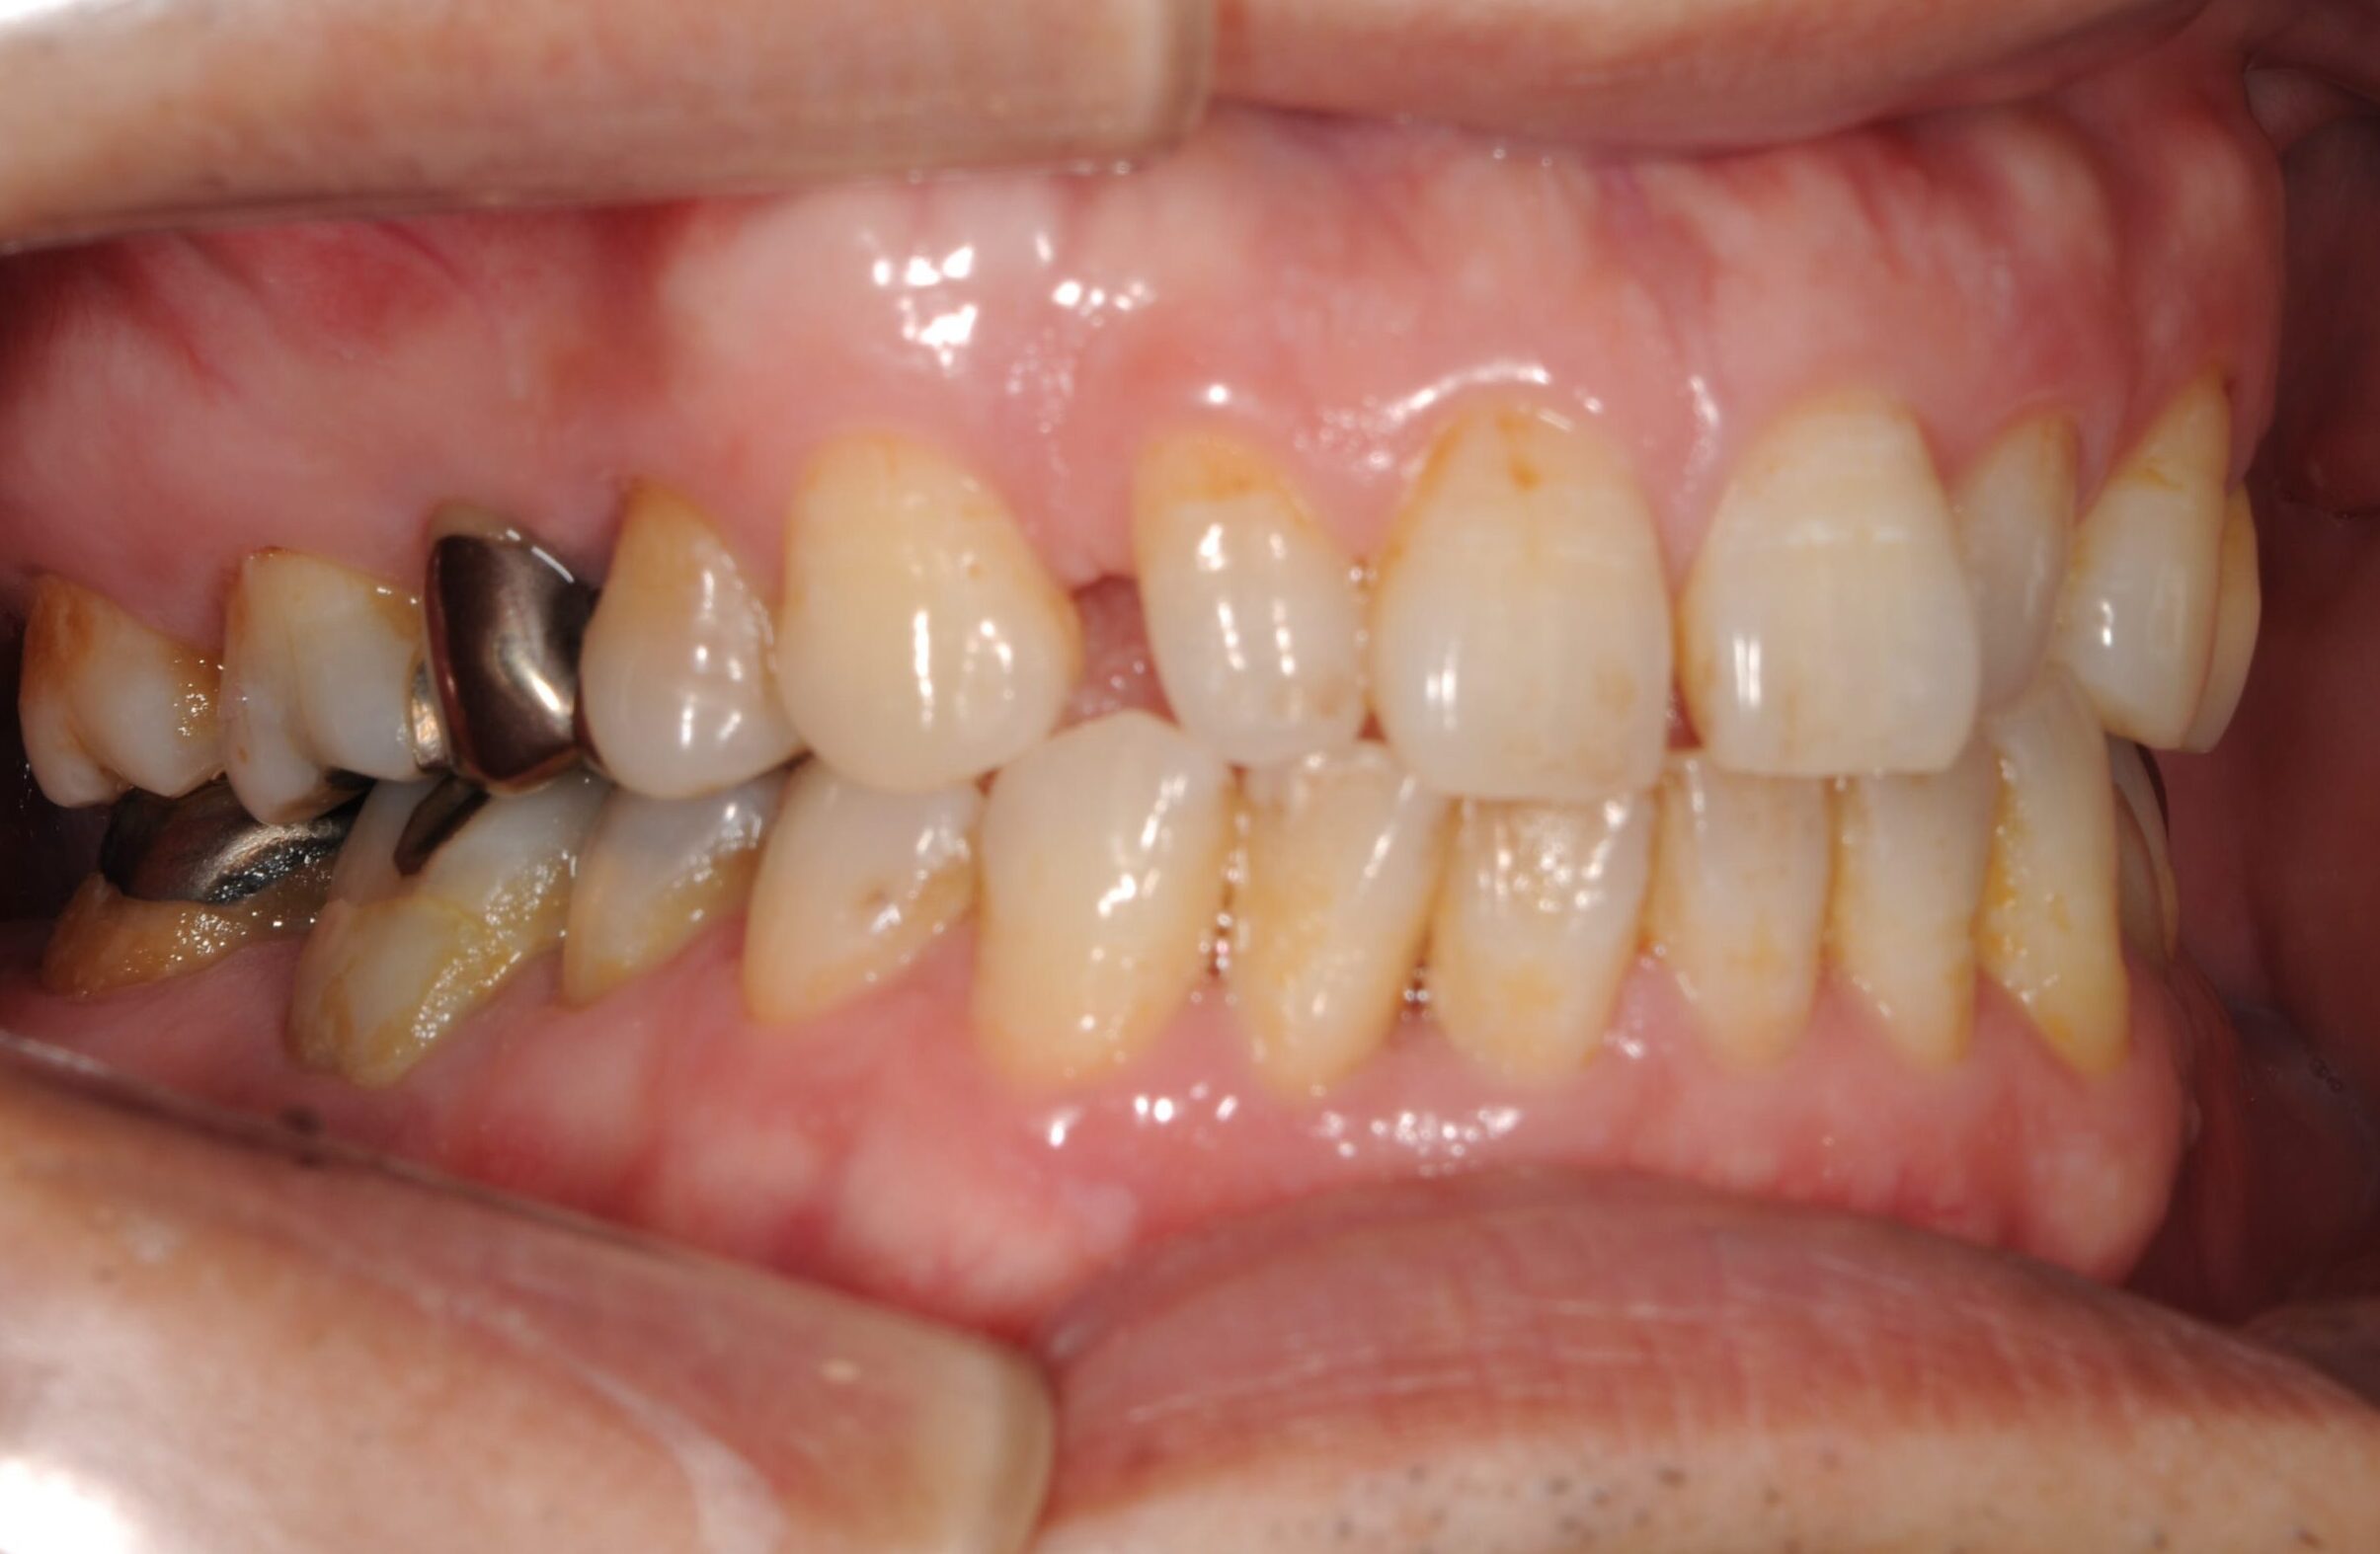

50代・男性

奥歯が欠けた|下顎左右6番の抜歯に伴うインプラント治療

before

治療前

症例写真 before

左右の下の奥歯が欠けたという主訴で来院されました。

診断の結果、下顎左右6番の根尖性歯周炎と2次虫歯が認められました。

どちらの歯も状態が悪く保存的処置が望めませんでした。患者さんとの相談の結果、抜歯しインプラントを埋入することになりました。

まず右下6番の抜歯、インプラント埋入手術、上部構造の装着を行い、次いで左下6番の治療を右下同様に進めました。

上部構造装着後10年以上経過しますが、定期的なメインテナンスと患者さんの日々のケアの甲斐あって、現在まで良好な経過をたどっています。